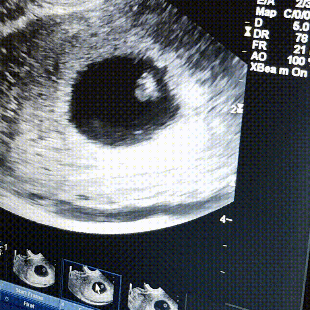

Сходила на узи 6н+6д. + видео 😍😍😍

Результаты: УЗИ, КТГ, доплера, скринингаОх и паникерша я конечно!)) Хотя как только пришёл положительный хгч была спокойна как стена, а потом начались страхи какие-то, переживания, розовые выделения, которые добили меня морально. Думала буду держаться до последнего и в 10 недель схожу на узи, но не вышло. По УЗИ все хорошо, отслоек нет, тонуса тоже, беременность в матке (ну в этом я не сомневалась), строк по месячным 6н+6д, по УЗИ намерили 6н+2д. Но овуляция была неизвестно когда, последний раз цикл до б был 30 дней, поэтому может быть небольшая разница, это нормально. Я не могла успокоиться пока своими глазами не увидела ребятёнка ❤😍 на видео видно как быстро бьётся сердечко, все я спокойна, не знаю правда на сколько меня хватит еще 😂 Предположили, что розовые выделения это закрепление, потому что плод крепится до 8-10 недель (такое я уже не раз слышала). Ну и видео добавляю 😍